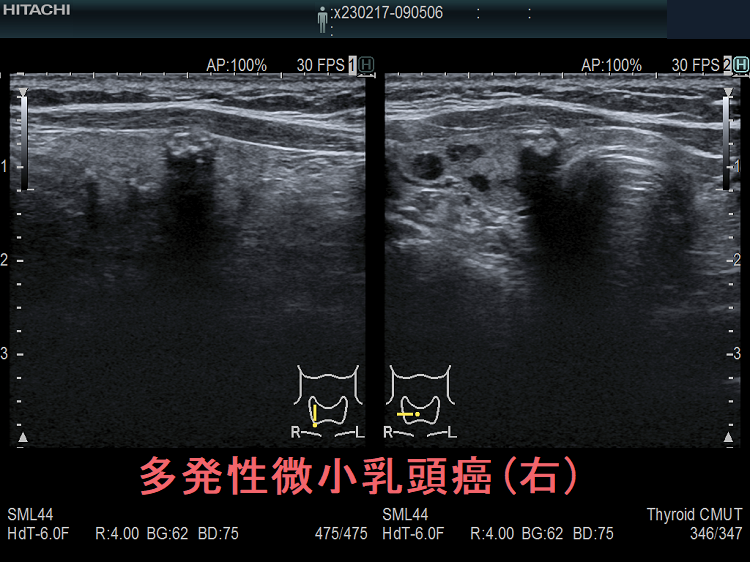

多発性の甲状腺微小乳頭癌

多発性の甲状腺微小乳頭癌は、リンパ節転移しやすいとされます(Am J Surg. 2014 Sep;208(3):412-8.)。